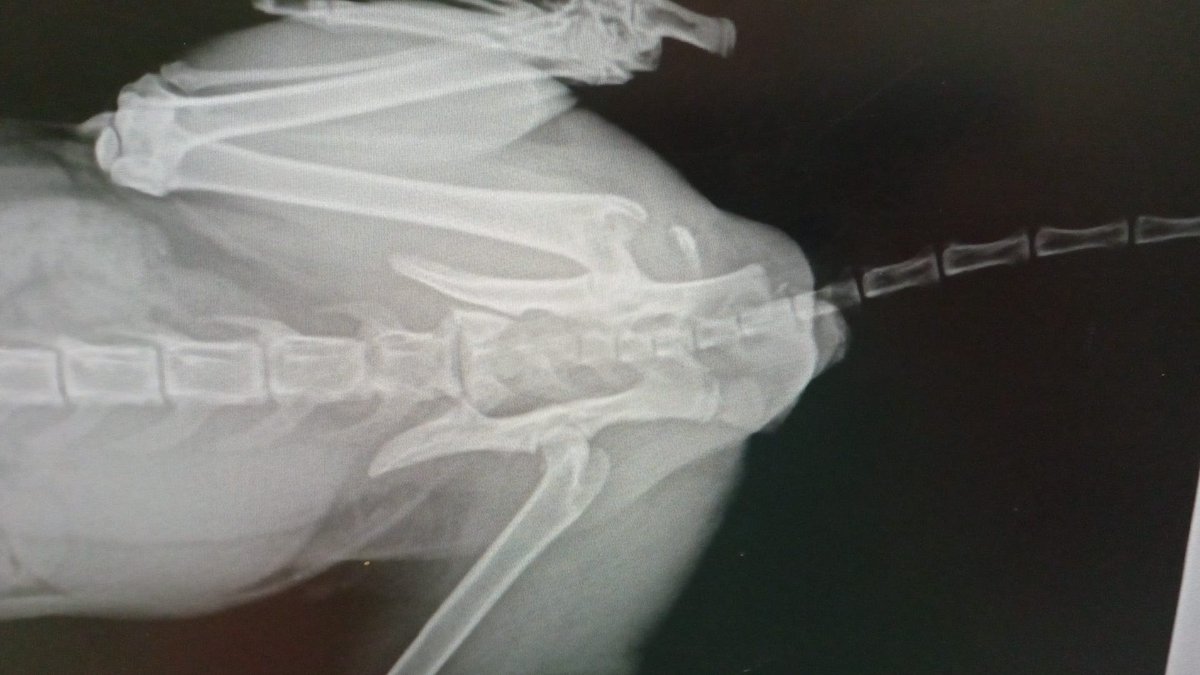

💔 AYUDA URGENTE PARA BLAS 💔 Encontrado tras un probable atropello el 3 de febrero en #Torrent, #Valencia (entrada desde Picanya). 🦴 Fractura de húmero ⚠️ Luxación sacroilíaca Sin ayudas públicas. Necesitamos ayuda urgente. ➡️ Código Bizum ONG: 0️⃣0️⃣8️⃣1️⃣5️⃣ 💳 Caixa Popular...

AsociacionADAT's tweet image. 💔 AYUDA URGENTE PARA BLAS 💔

Encontrado tras un probable atropello el 3 de febrero en #Torrent, #Valencia (entrada desde Picanya).

🦴 Fractura de húmero

⚠️ Luxación sacroilíaca

Sin ayudas públicas. Necesitamos ayuda urgente.

➡️ Código Bizum ONG: 0️⃣0️⃣8️⃣1️⃣5️⃣

💳 Caixa Popular...